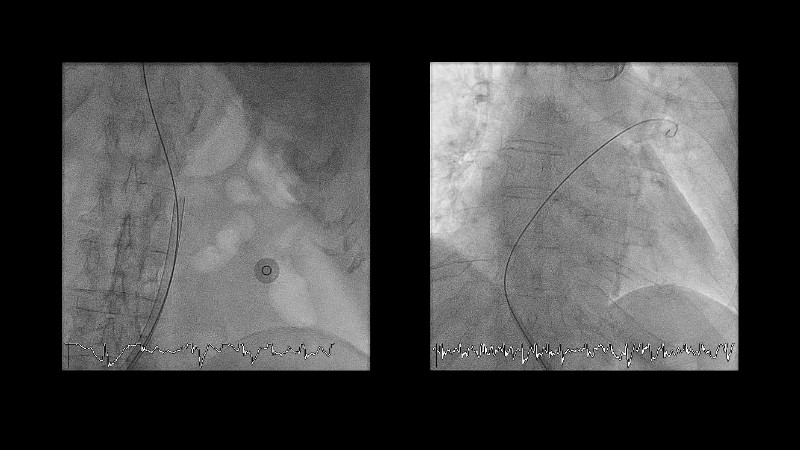

Explore the forefront of left atrial appendage (LAA) closure with this session focusing on the latest innovations and clinical opportunities. Topics include recent data on WATCHMAN FLX PRO and VersaCross Connect systems, workflow strategies to improve procedural efficiency, and discussions on upcoming clinical trials such as CHAF and LAAOS IV, emphasizing expanding stroke prevention options beyond bleeding risk reduction.

- To learn workflow strategies to improve efficiencies for LAA closure - VersaCross Connect + PRO + TruSteer